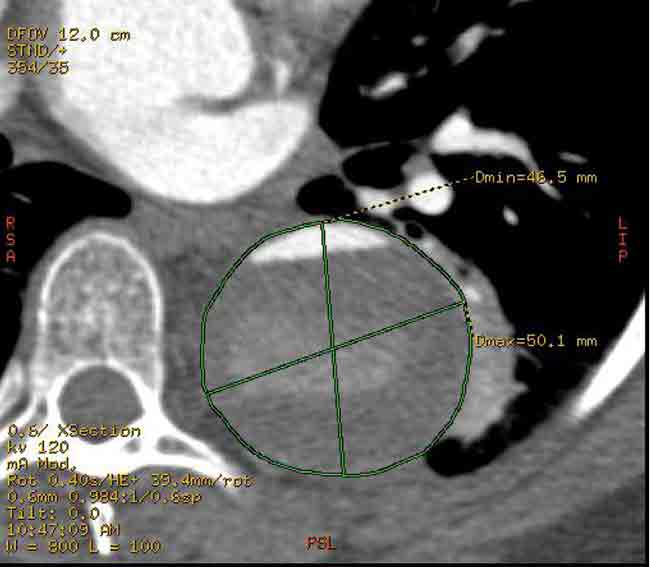

After performing a right groin cutdown and exposing the right common femoral artery, we exchanged our regular .035” guidewire for a stiff .035” guidewire. We used IVUS to confirm that the wire was entirely in the true lumen. We then inserted a 37 mm x 20 cm Gore TAG endoluminal graft over the guidewire and deployed it just beyond the left subclavian artery. We sized the diameter of the endoluminal graft based off of the diameter of the aorta just beyond the left subclavian artery. We allowed a 10% over sizing of the endoluminal graft to permit adequate proximal seal and fixation. Distally this would mean a significant oversizing of the endoluminal graft because the true lumen was significantly compressed. A completion aortogram demonstrated excellent seal proximally with no evidence of filling of the false lumen proximally. Distally there was some retrograde filling of the false lumen which is to be expected. The true lumen was also slightly expanded due to the oversizing of the endograft distally. With IVUS and aortography, we carefully inspected the septum distal to the stent graft above the celiac artery and there were no other signs of active communication between the two lumens.